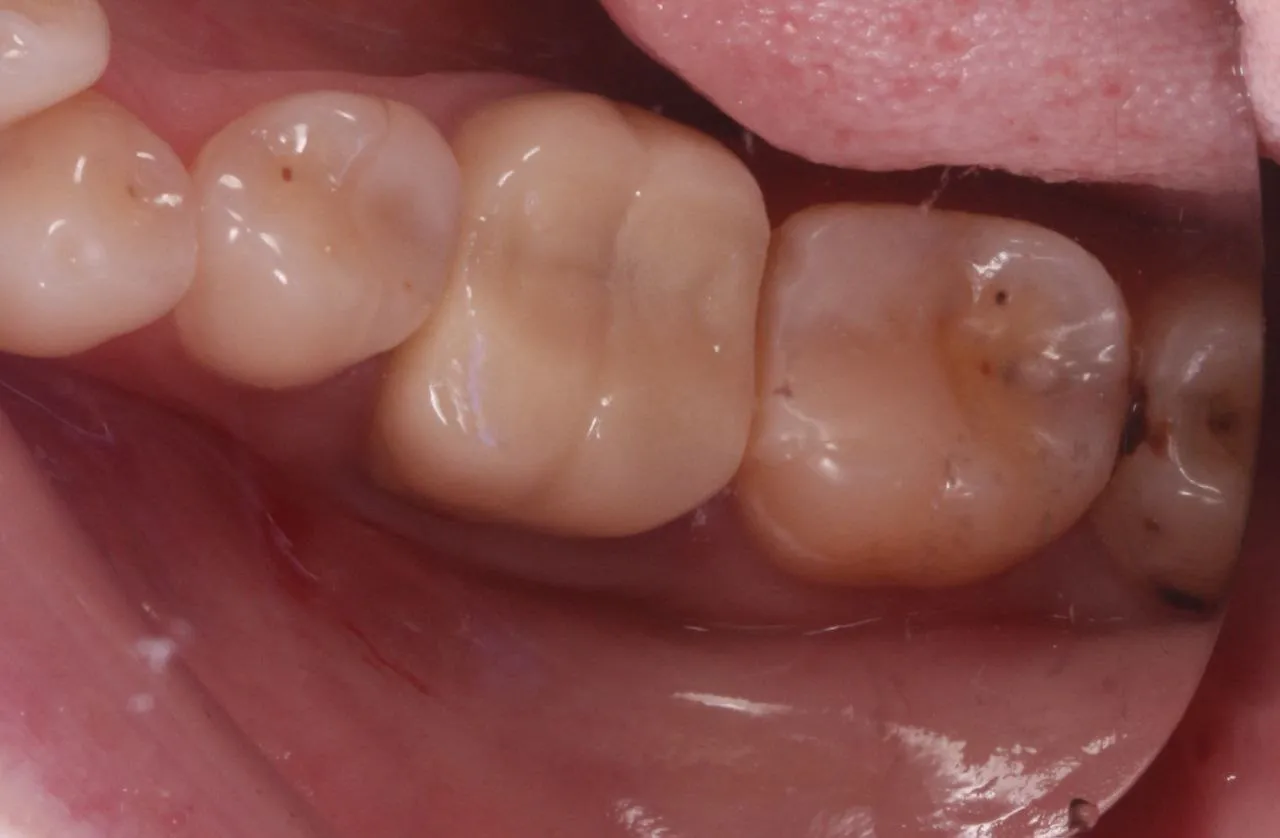

Лікування глибокого вторинного карієса зубів 17 та 16

Лікування вторинного карієсу в зубах 47 та 45